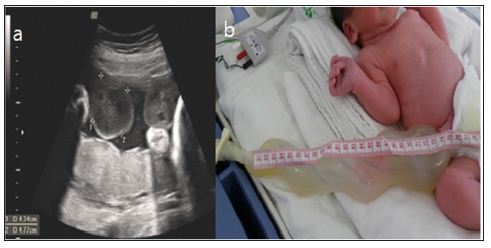

A male infant weighing 2420g was born at 36 weeks of gestation by cesarean section to a 31-year-old mother. The Apgar scores were 9 and 10 at 1 and 5minutes, respectively. Routine ultrasonography conducted in the 16th week of gestation showed cystic changes in the umbilicus, and chromosomal examination of amniotic fluid conducted in the 20th week of gestation showed 46, XY, inv (9) (p12q13). However, fetal development was progressing successfully. At delivery, the infant presented with a diffuse giant umbilical cord measuring 25cm in length and cm in diameter with a glistening surface and hydropic consistency (Figure 1). No abdominal contents were noted within the cord. The cord was clamped approximately 30cm from the abdominal wall, where it became thinner. Ultrasonography conducted when the infant was 2 days old showed a probable connection between the umbilicus and bladder, which was confirmed by a fistulogram.

Figure 1: a. Prenatal ultrasonography image in the 34th week of gestation showing the dilated umbilical cord with edema and b. Postnatal findings of the neonate with a diffuse giant umbilical cord.

The dried umbilical stump detached after 14 days, but a granulomatous structure remained, and persistent umbilical fluid loss from the clamped umbilicus indicated urine leakage. Operative exploration was conducted via an infra umbilical incision when the infant was 16 days old. The umbilical cord was contiguous with aurachal remnant (Figure 2). Excision and repair of the urachal remnant was completed. Histological examination of the umbilical cord confirmed the presence of focal edema with no epithelial lining. On postoperative day 9, a fistulogram showed no evidence of leakage in the bladder. The infant was discharged in good health, and all follow-up examinations were normal.